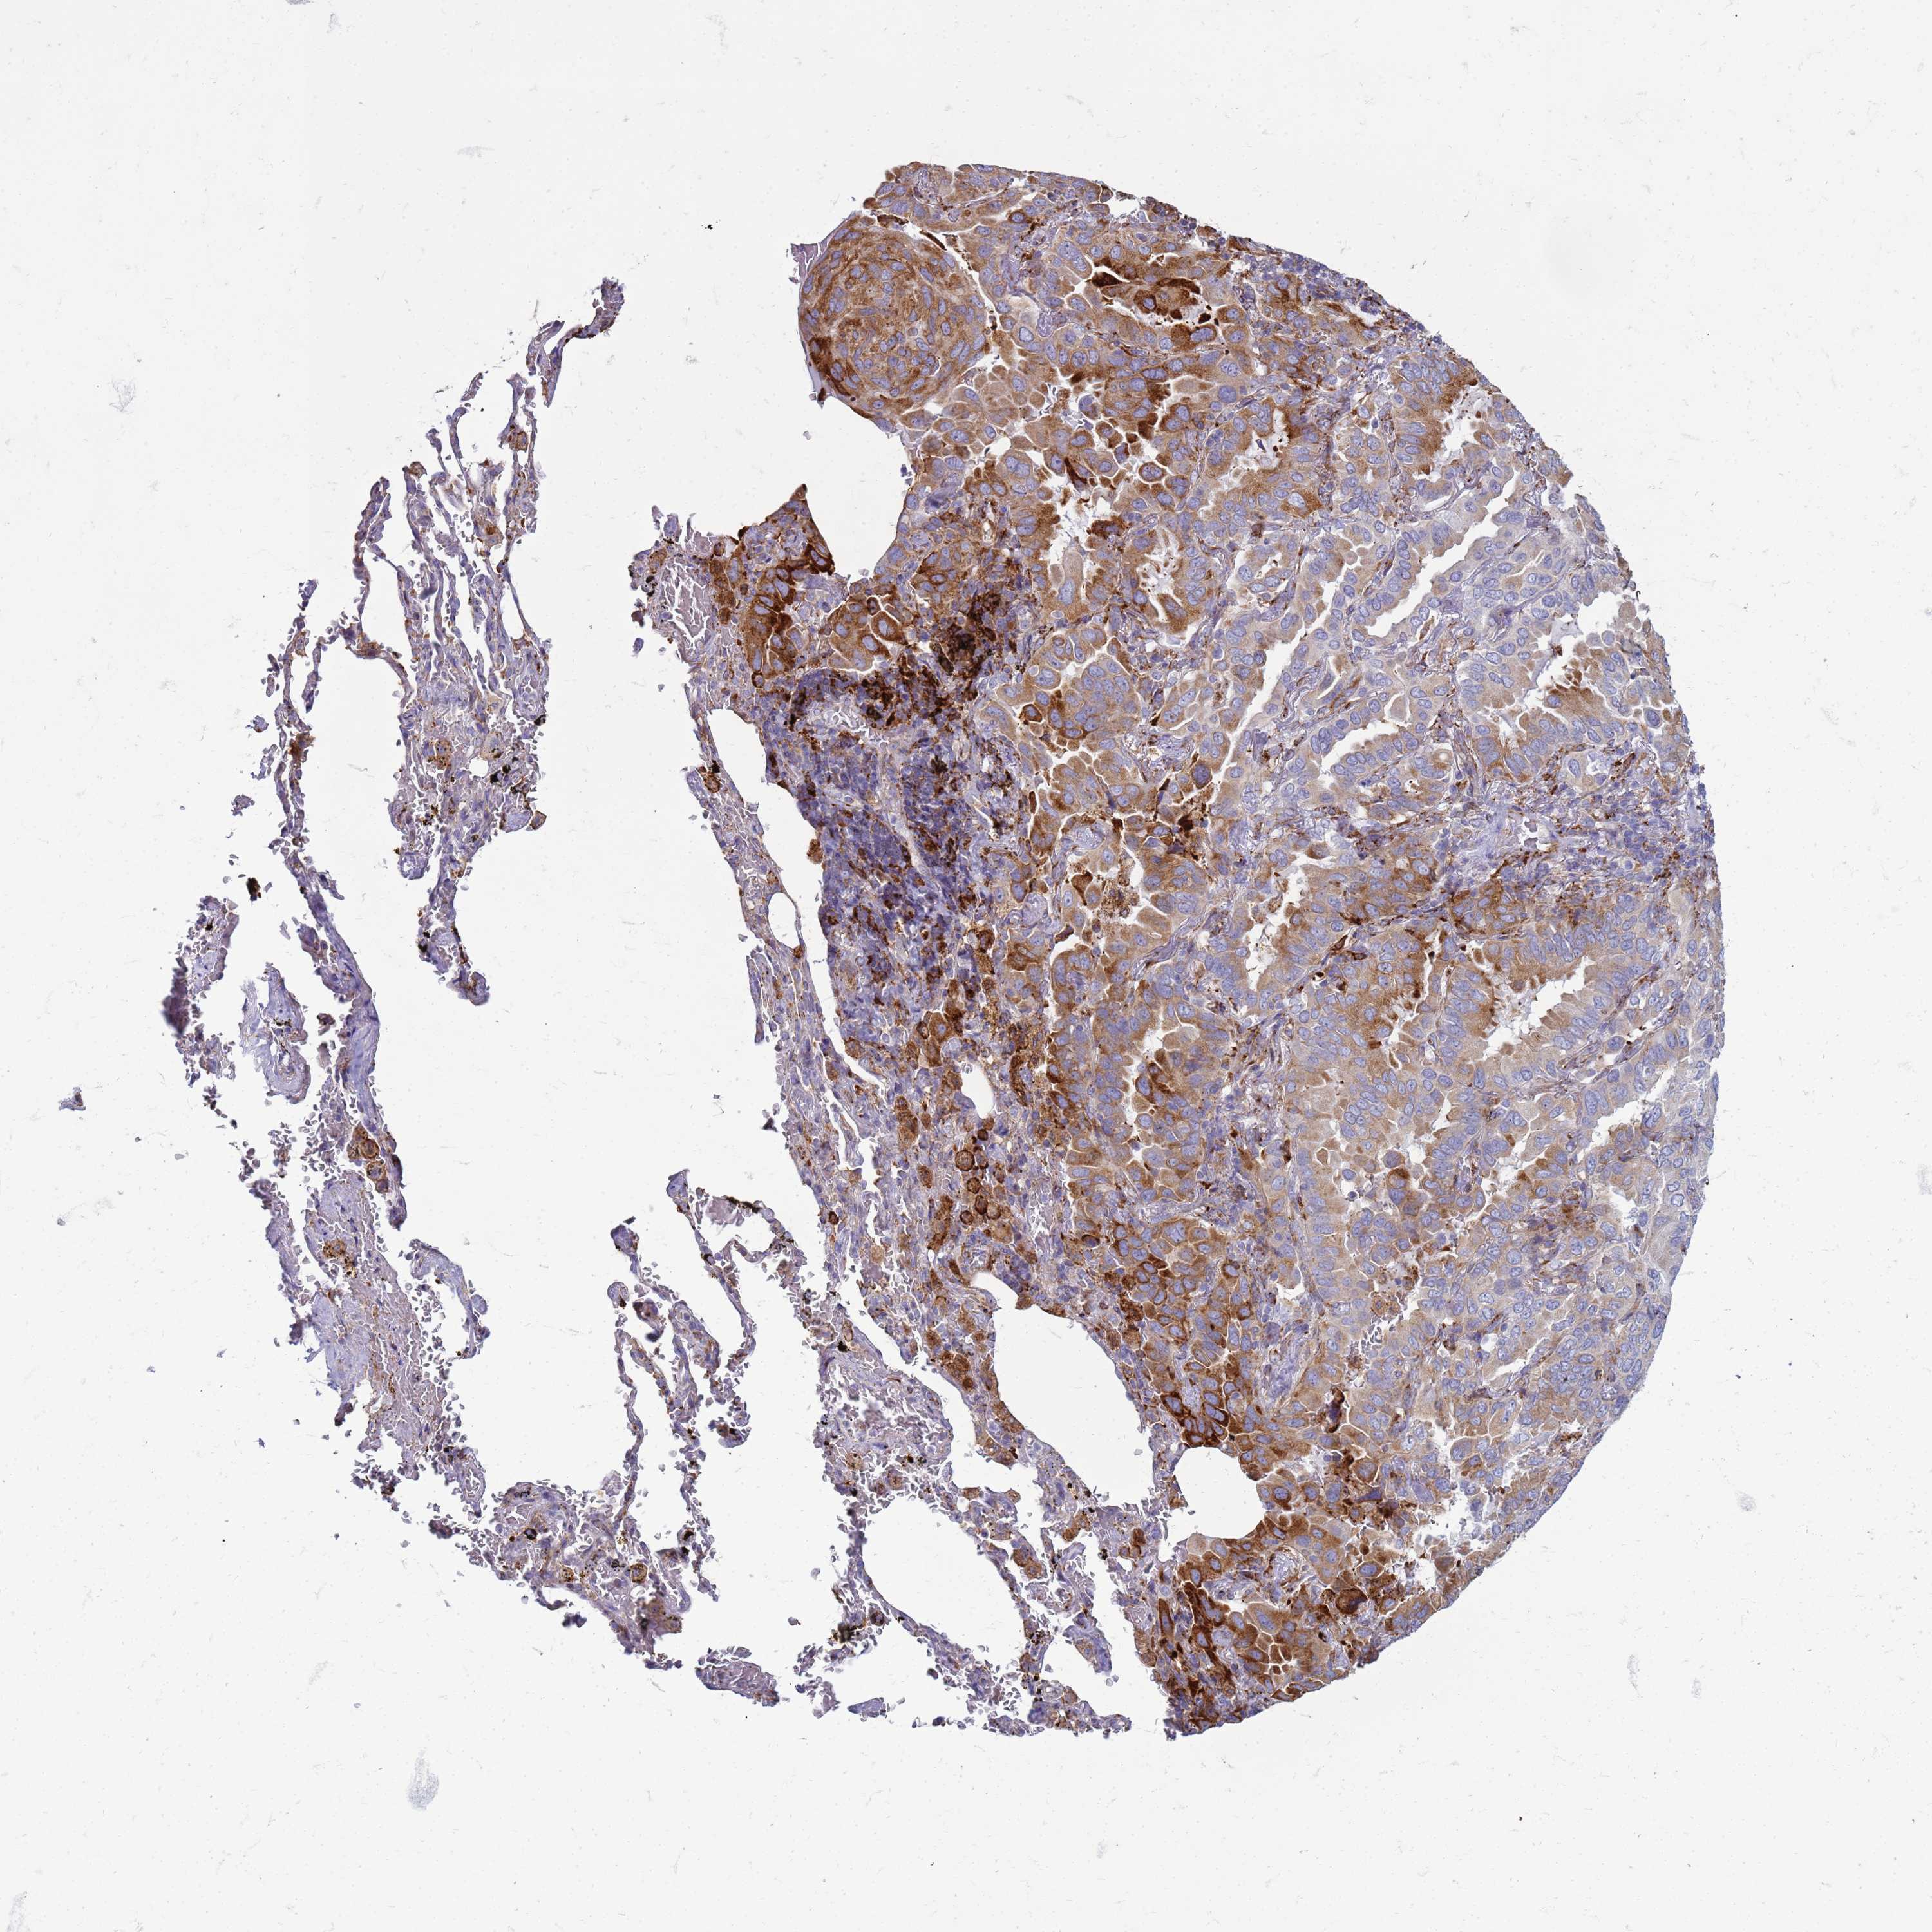

LUNG ADENOCARCINOMA (VALIDATION) - Interactive survival scatter ploti

The Survival Scatter plot shows the clinical status (i.e. dead or alive) for all individuals in the patient cohort, based on the same data that underlies the corresponding Kaplan-Meier plots. Patients that are alive at last time for follow-up are shown in blue and patients who have died during the study are shown in red.

The x-axis shows the expression levels (FPKM) of the investigated gene in the tumor tissue at the time of diagnosis. The y-axis shows the follow-up time after diagnosis (years). Both axes are complimented with kernel density curves demonstrating the data density over the axes. The top density plot shows the expression levels (FPKM) distribution among dead (red) and alive patients (blue). The right density plot shows the data density of the survived years of dead patients with high and low expression levels respectively, stratified using the cutoff indicated by the vertical dashed line through the Survival Scatter plot. This cutoff is automatically defined based on the FPKM cutoff that minimizes the p-score. The cutoff can be changed by dragging the vertical line or by entering a cutoff value in the square labeled "Current cut-off".

Under the Survival Scatter plot the p-score landscape (black curve; left axis) is shown together with dead median separation (red curve; right axis). Dead median separation is the difference in median mRNA expression between patients who have died with high and low expression, respectively. It is calculated as follows: median FPKM expression of dead patients with high expression - median FPKM expression of dead patients with low expression. This is intended to aid the user in visually exploring custom cutoffs and the associated p-scores and dead median separation.

Individual patient data is displayed and can be filtered by clicking on one or more of the category buttons on the top of the page. Categories describing expression level and patient information include: high, low, alive, dead, female, male and tumor stages. The scale of the x-axis can be toggled between linear and log-scale by clicking on the "x log" button. Mouse-over function shows TCGA ID, patient information and mRNA expression (FPKM) for each patient.

& Survival analysisi

Kaplan-Meier plots summarize results from analysis of correlation between mRNA expression level and patient survival. Patients were divided based on level of expression into one of the two groups "low" (under cut off) or "high" (over cut off). X-axis shows time for survival (years) and y-axis shows the probability of survival, where 1.0 corresponds to 100 percent.

PDK3 is potential prognostic, high expression is unfavorable in Lung Adenocarcinoma (validation)

Best expression cut offi

Based on the FPKM value of each gene, patients were classified into two groups and association between prognosis (survival) and gene expression (FPKM) was examined. The best expression cut-off refers the FPKM value that yields maximal difference with regard to survival between the two groups at the lowest log-rank P-value. Best expression cut-off was selected based on survival analysis .

When clicking on this number, the vertical dashed line indicating cut-off, the interactive survival plot, and the Kaplan-Meier curve will be adjusted to show results based on the best expression cut-off.

: 7.03

P scorei

Log-rank P value for Kaplan-Meier plot showing results from analysis of correlation between mRNA expression level and patient survival.

N/A

5-year survival highi

5-year survival for patients with higher expression than the expression cutoff.

For melanoma and glioma, 3-year survival is shown.

5-year survival lowi

5-year survival for patients with lower expression than the expression cutoff.

TCGA RNA samplesi

RNA-seq data is reported as average FPKM (number Fragments Per Kilobase of exon per Million reads), generated by the The Cancer Genome Atlas (TCGA) .

Normal distribution across the dataset is visualized with box plots, shown as median and 25th and 75th percentiles. Points are displayed as outliers if they are above or below 1.5 times the interquartile range. FPKM values of the individual samples are presented next to the box plot.

Average pTPM 7.8

Number of samples 105